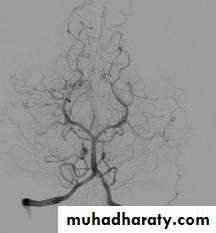

Cerebral angiography (the gold standard for evaluation of cerebral angiography) and can also demonstrate cerebral vasospasm

Angiographic vasospasm: asymptomatic arterial narrowing seen on angiography

Cerebral angiography

Intra-arterial Balloon dilatation

Intra-arterial papaverine injection